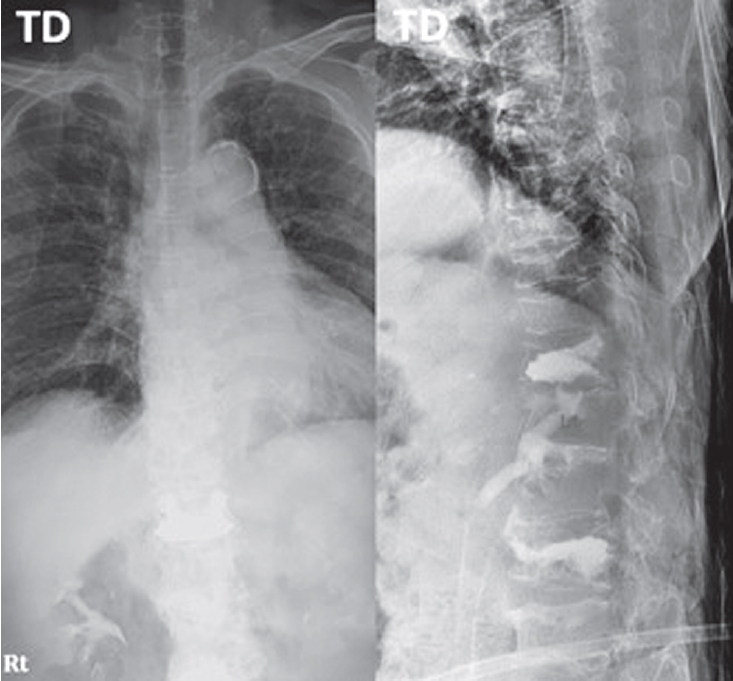

An 85-year-old woman presented with acute back pain after falling on an escalator. Neurological examination showed no motor or sensory deficits and no bowel or bladder dysfunction. Her medical history included vertebroplasty for T12 and L3 compression fractures and a right subtrochanteric femoral fracture treated with plate fixation. After the femoral fracture surgery, she had received intravenous bisphosphonate therapy at 3-month intervals for two years. Initial radiographs revealed multiple chronic vertebral compression fractures, and computed tomography identified a new L2 compression fracture (Fig. 1).

Fig. 1.

Initial lumbar spine anteroposterior and lateral radiographs demonstrating an acute L2 compression fracture and multiple chronic compression fractures and prior vertebroplasty at T12, L3.

Fig. 1. Initial lumbar spine anteroposterior and lateral radiographs demonstrating an acute L2 compression fracture and multiple chronic compression fractures and prior vertebroplasty at T12, L3.